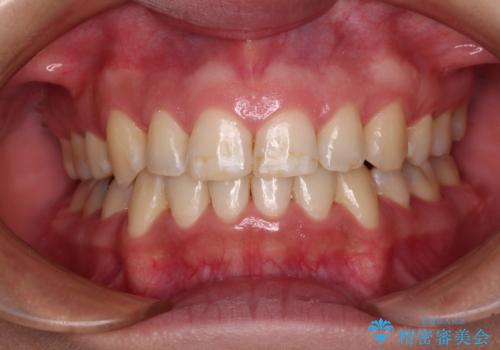

前歯のデコボコを短期間で解消 ワイヤー装置による抜歯矯正

当初予定は2年半程度と伝えていましたが、2年にも満たない期間で治療を終えることができました。